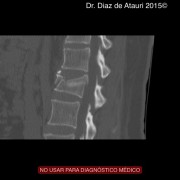

Puedes ver imágenes de una fractura y de la técnica quirúrgica de un caso real del 2015 tras este texto.